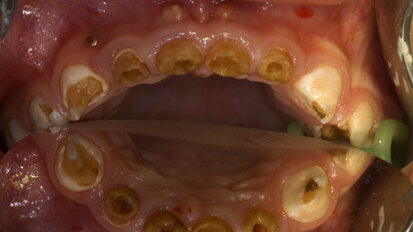

Herausforderung: Frühkindliche Karies

MÜNCHEN/LEIPZIG – Mehr als 1.200 Teilnehmerinnen und Teilnehmer aus 75 Ländern reisten vom 17. bis 20. Juni 2009 nach München zu dem ...

Narkose bei schwerer Kinderkaries wieder planbar

OLDENBURG/LEIPZIG – Der Bundesverband der Kinderzahnärzte (BuKiZ), die Deutsche Gesellschaft für Kinderzahnheilkunde (DKG) und der ...